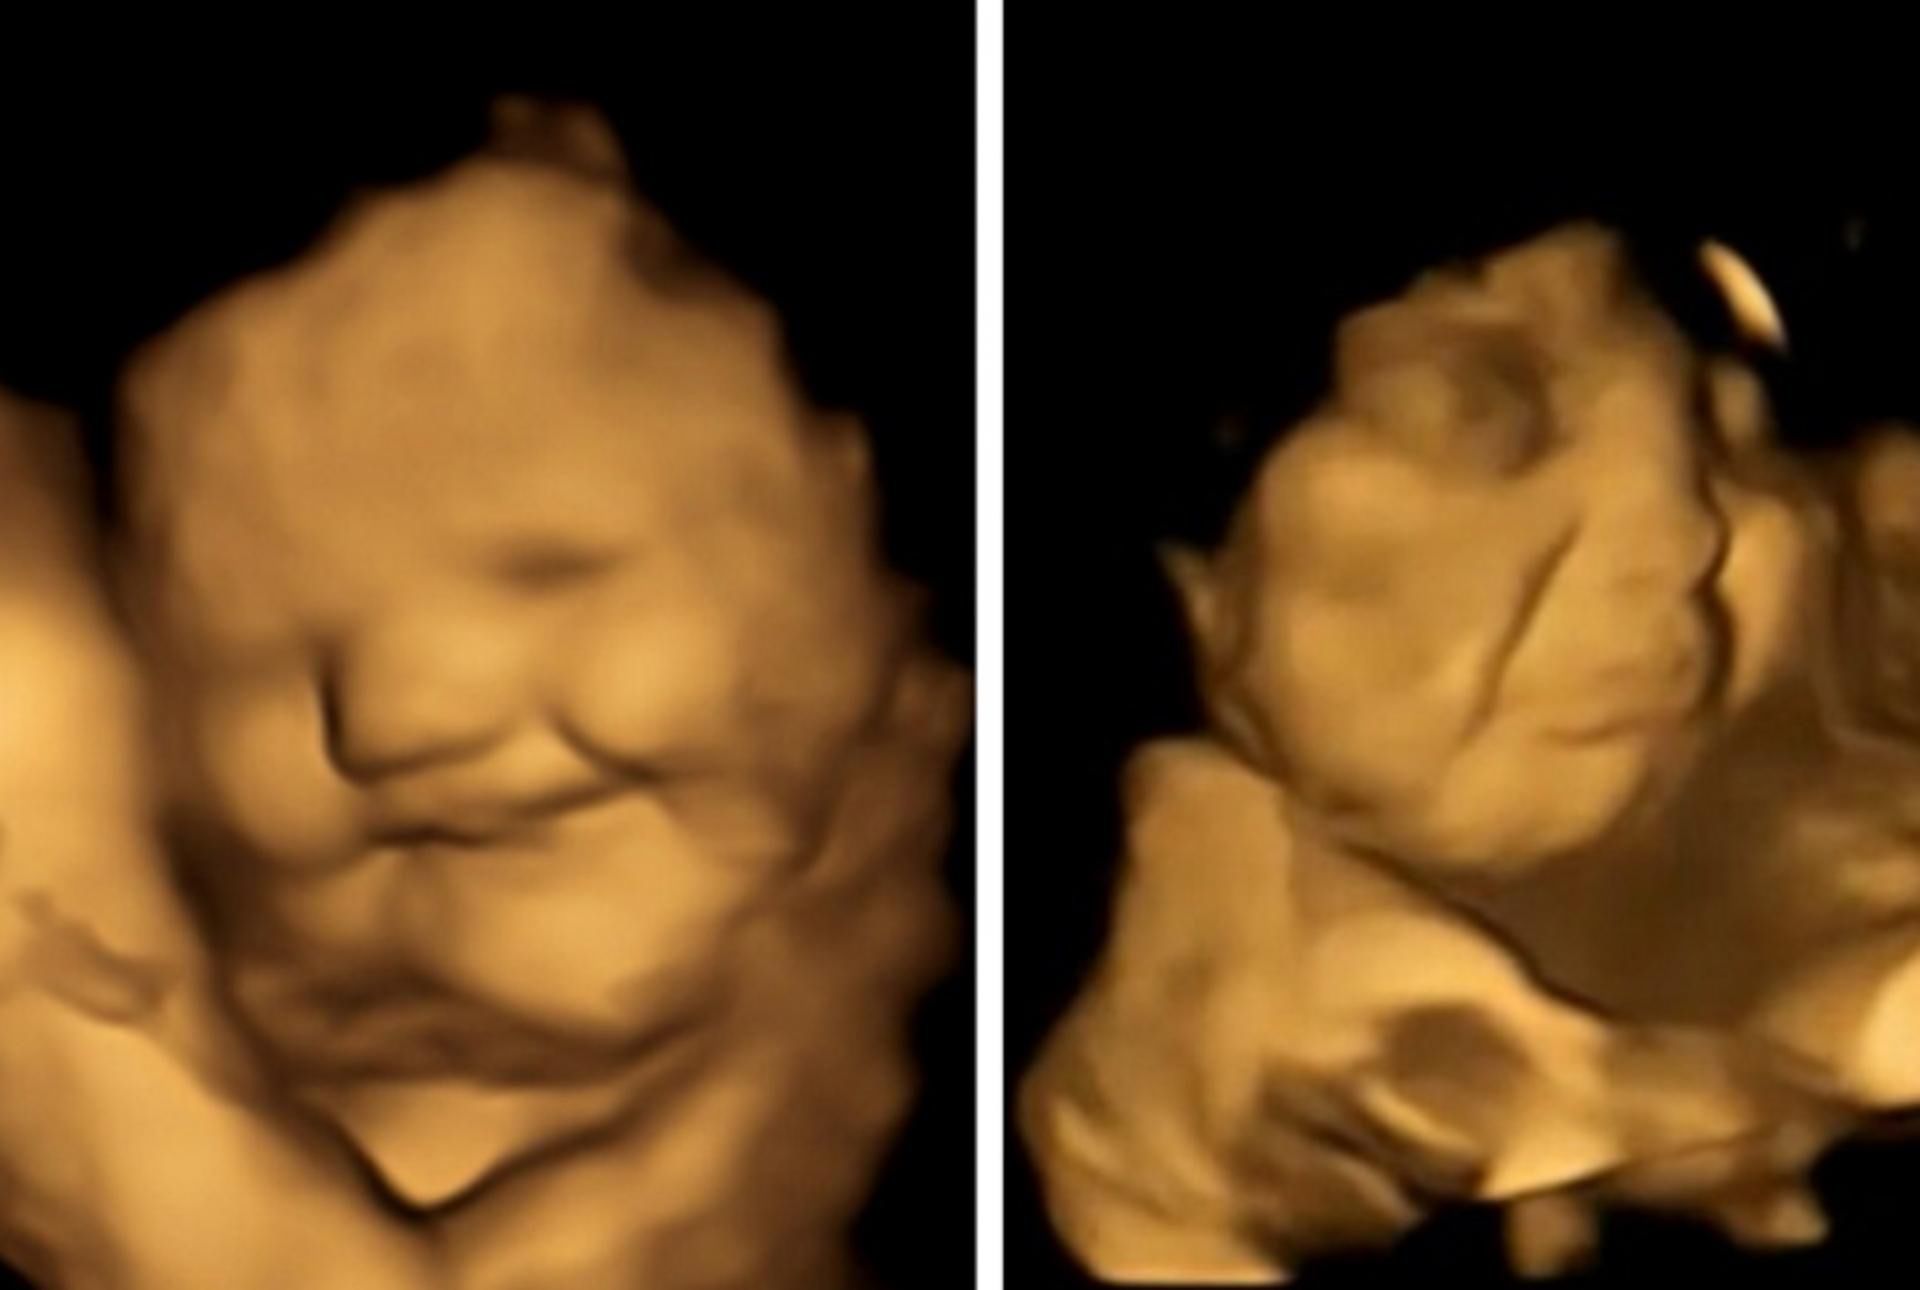

Naukowcy dostrzegli na zdjęciach, że gdy do maluchów docierał smak marchewki, na ich buziach pokazywał się grymas przypominający uśmiech. Natomiast po wyczuciu smaku jarmużu, twarze nienarodzonych dzieci wykrzywiały się jak do płaczu.

Reakcje nienarodzonych dzieci obserwowane w obu grupach (w porównaniu z tymi z grupy kontrolnej, które nie były narażone na żaden smak) wykazały, że ekspozycja na niewielką nawet ilość marchwi lub jarmużu wystarczyła do wywołania reakcji uśmiechu, lub płaczu.